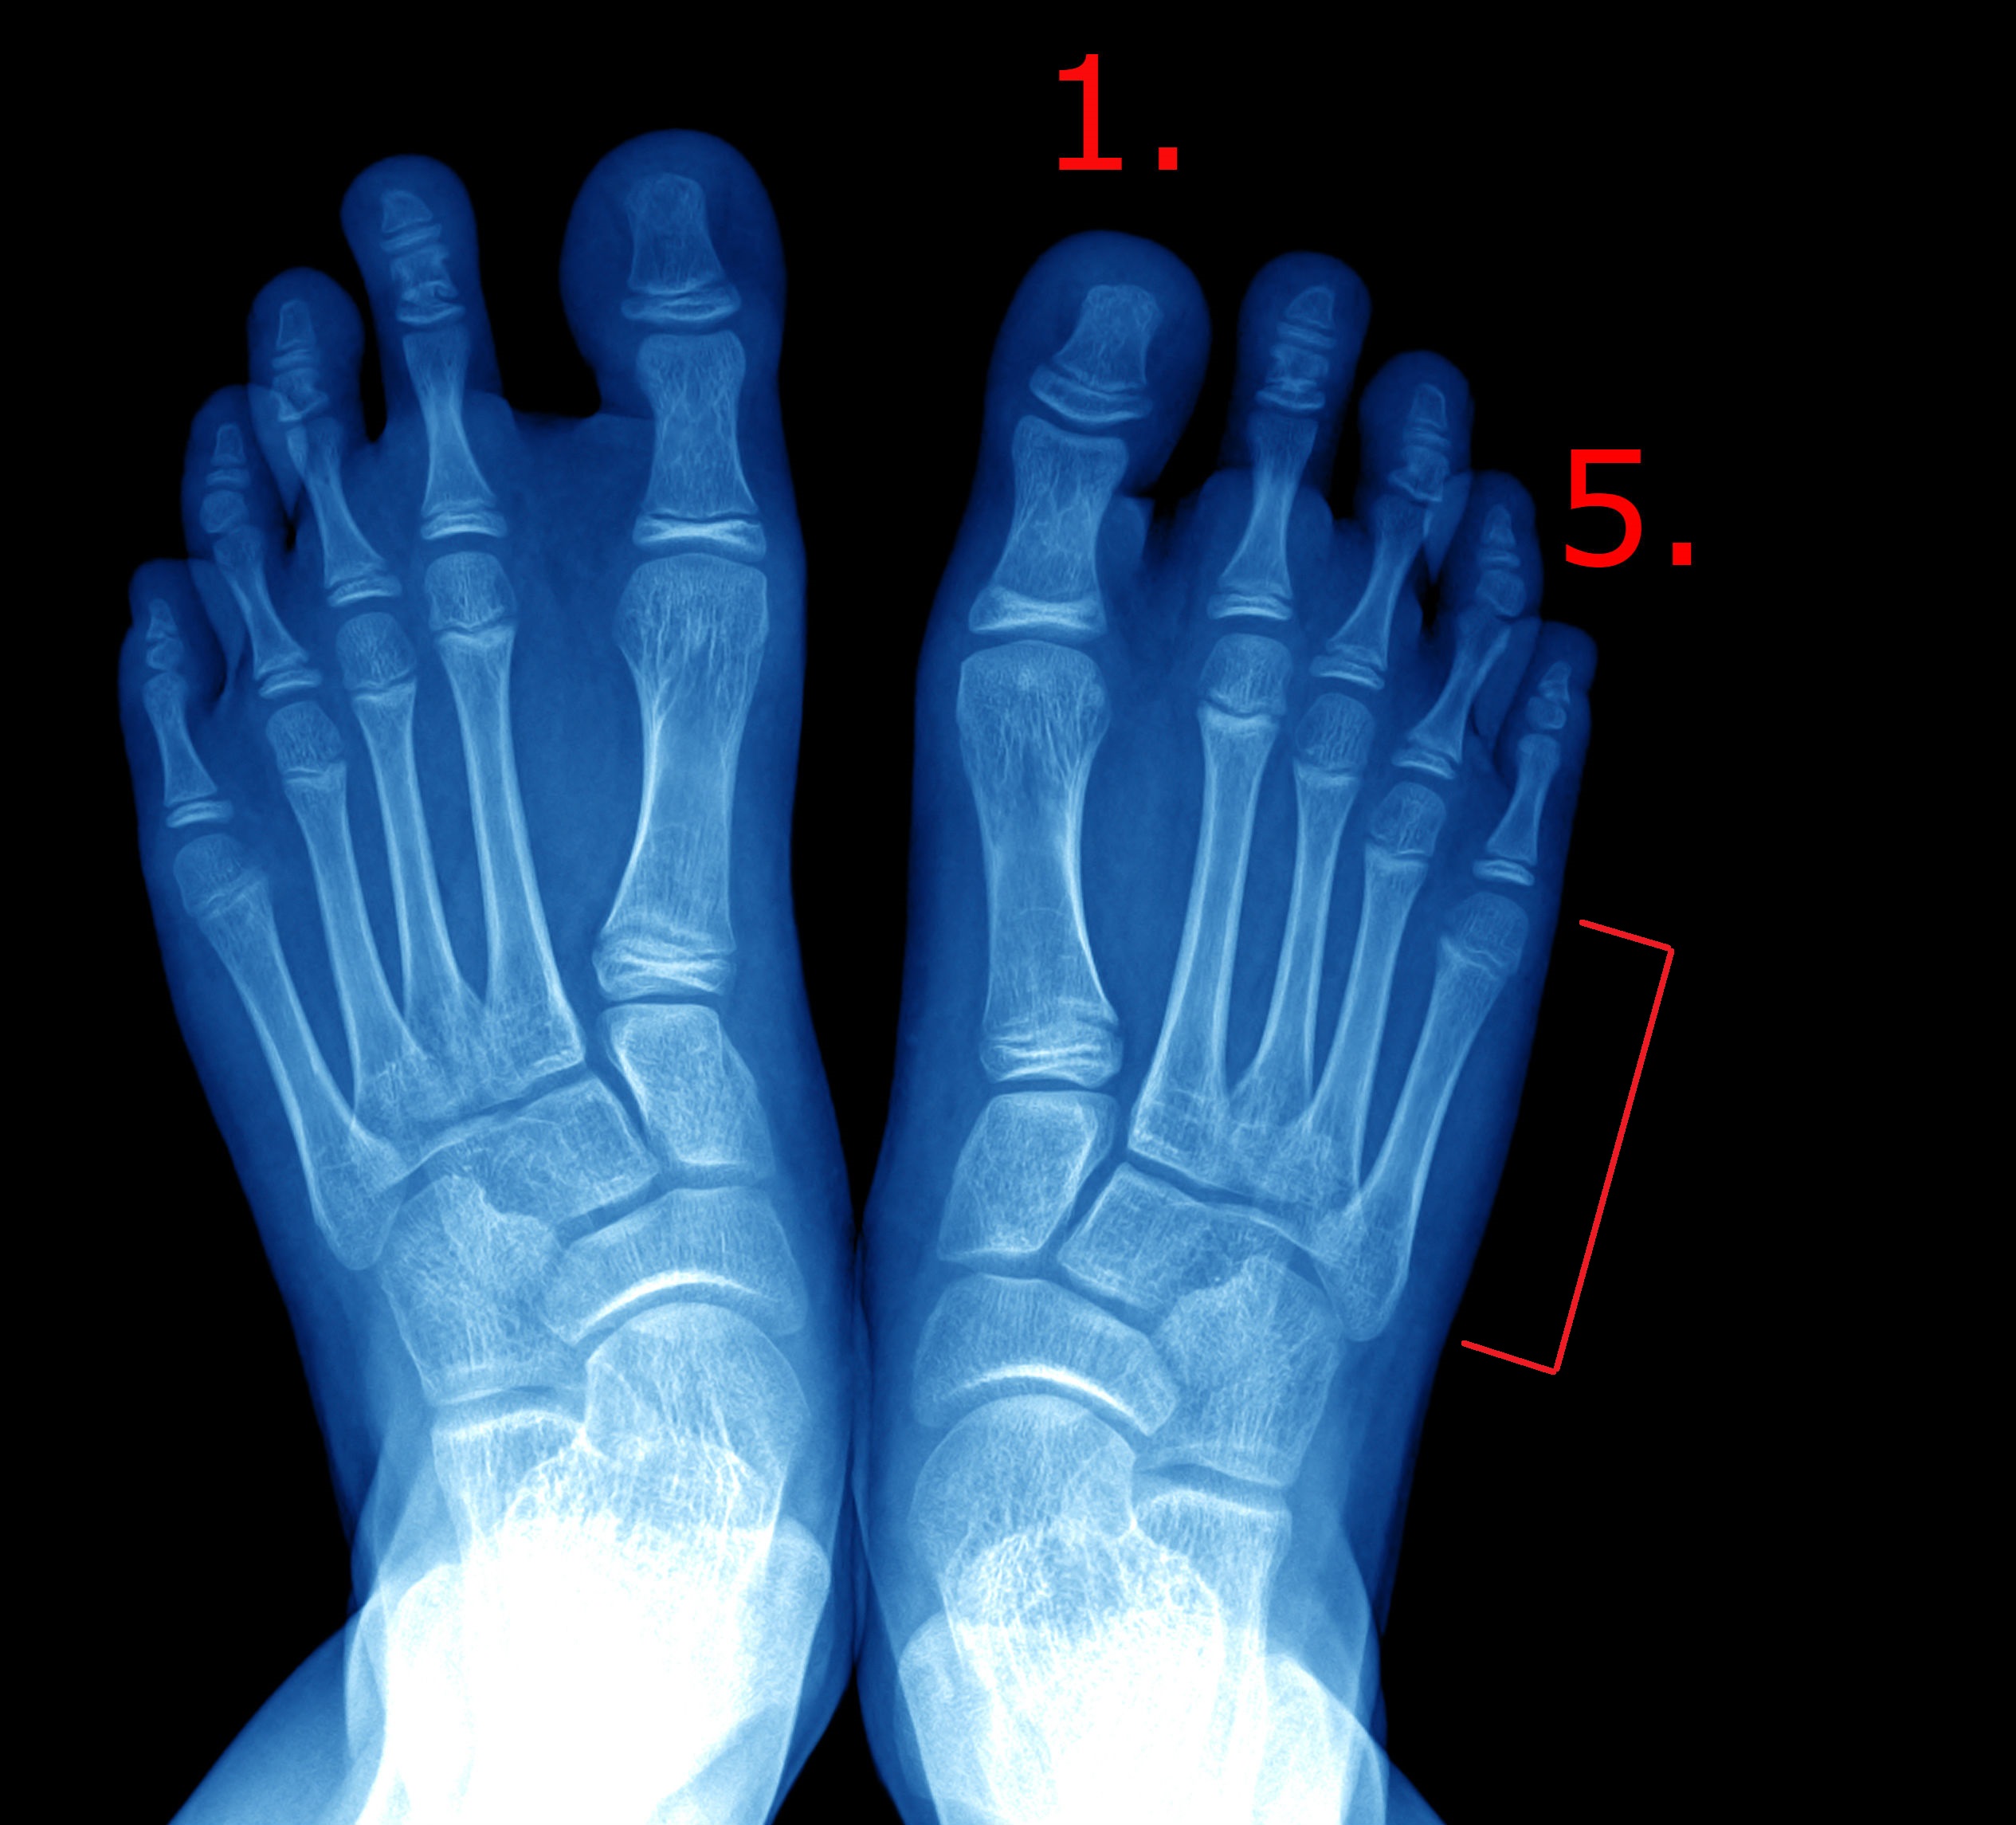

En spredfod er en tilstand, hvor mellemfodsknoglerne (se billede) er spredt fra hinanden. Der er to former for spredfod:

Ved den første type (metatarsus primus varus) er det kun første tåstråle (se billede), der spreder sig væk fra de øvrige fire mellemfodsknogler. Tåstrålen er den række knogler, der dannes af den første mellemfodsknogle og de efterfølgende tåknogler. Når man taler om første tåstråle, er det den tåstråle, der ender som storetåen, og femte tåstråle ender som lilletåen. Denne form for spredfod er arvelig, men den kan springe nogle generationsled over for så at dukke op igen.

- Ved den anden type spredfod (metatarsus latus) er det alle mellemfodens knogler, der spreder sig væk fra hinanden, så første og femte tåstråle peger "i hver sin retning". Dette giver en meget bred forfod. Der sker det, at fodens tværbue synker og derved spredes knoglerne. Dette er noget der udvikles gennem livet, men det kan hos enkelte ses fra ungdommen.

Dette kan gøres blot ved at se på foden. Det er ofte en god idé at få foretaget røntgen af fødderne. På et røntgenbillede kan man se knoglernes indbyrdes forhold, og om det har påvirket leddene mellem knoglerne. Hvis man overvejer at operere, skal lægen bruge røntgenbilleder til at bedømme knoglernes placering i forhold til hinanden samt vurdere leddene, og ud fra dette beslutte sig for hvilken operationsmetode, der eventuelt kan tilbydes.